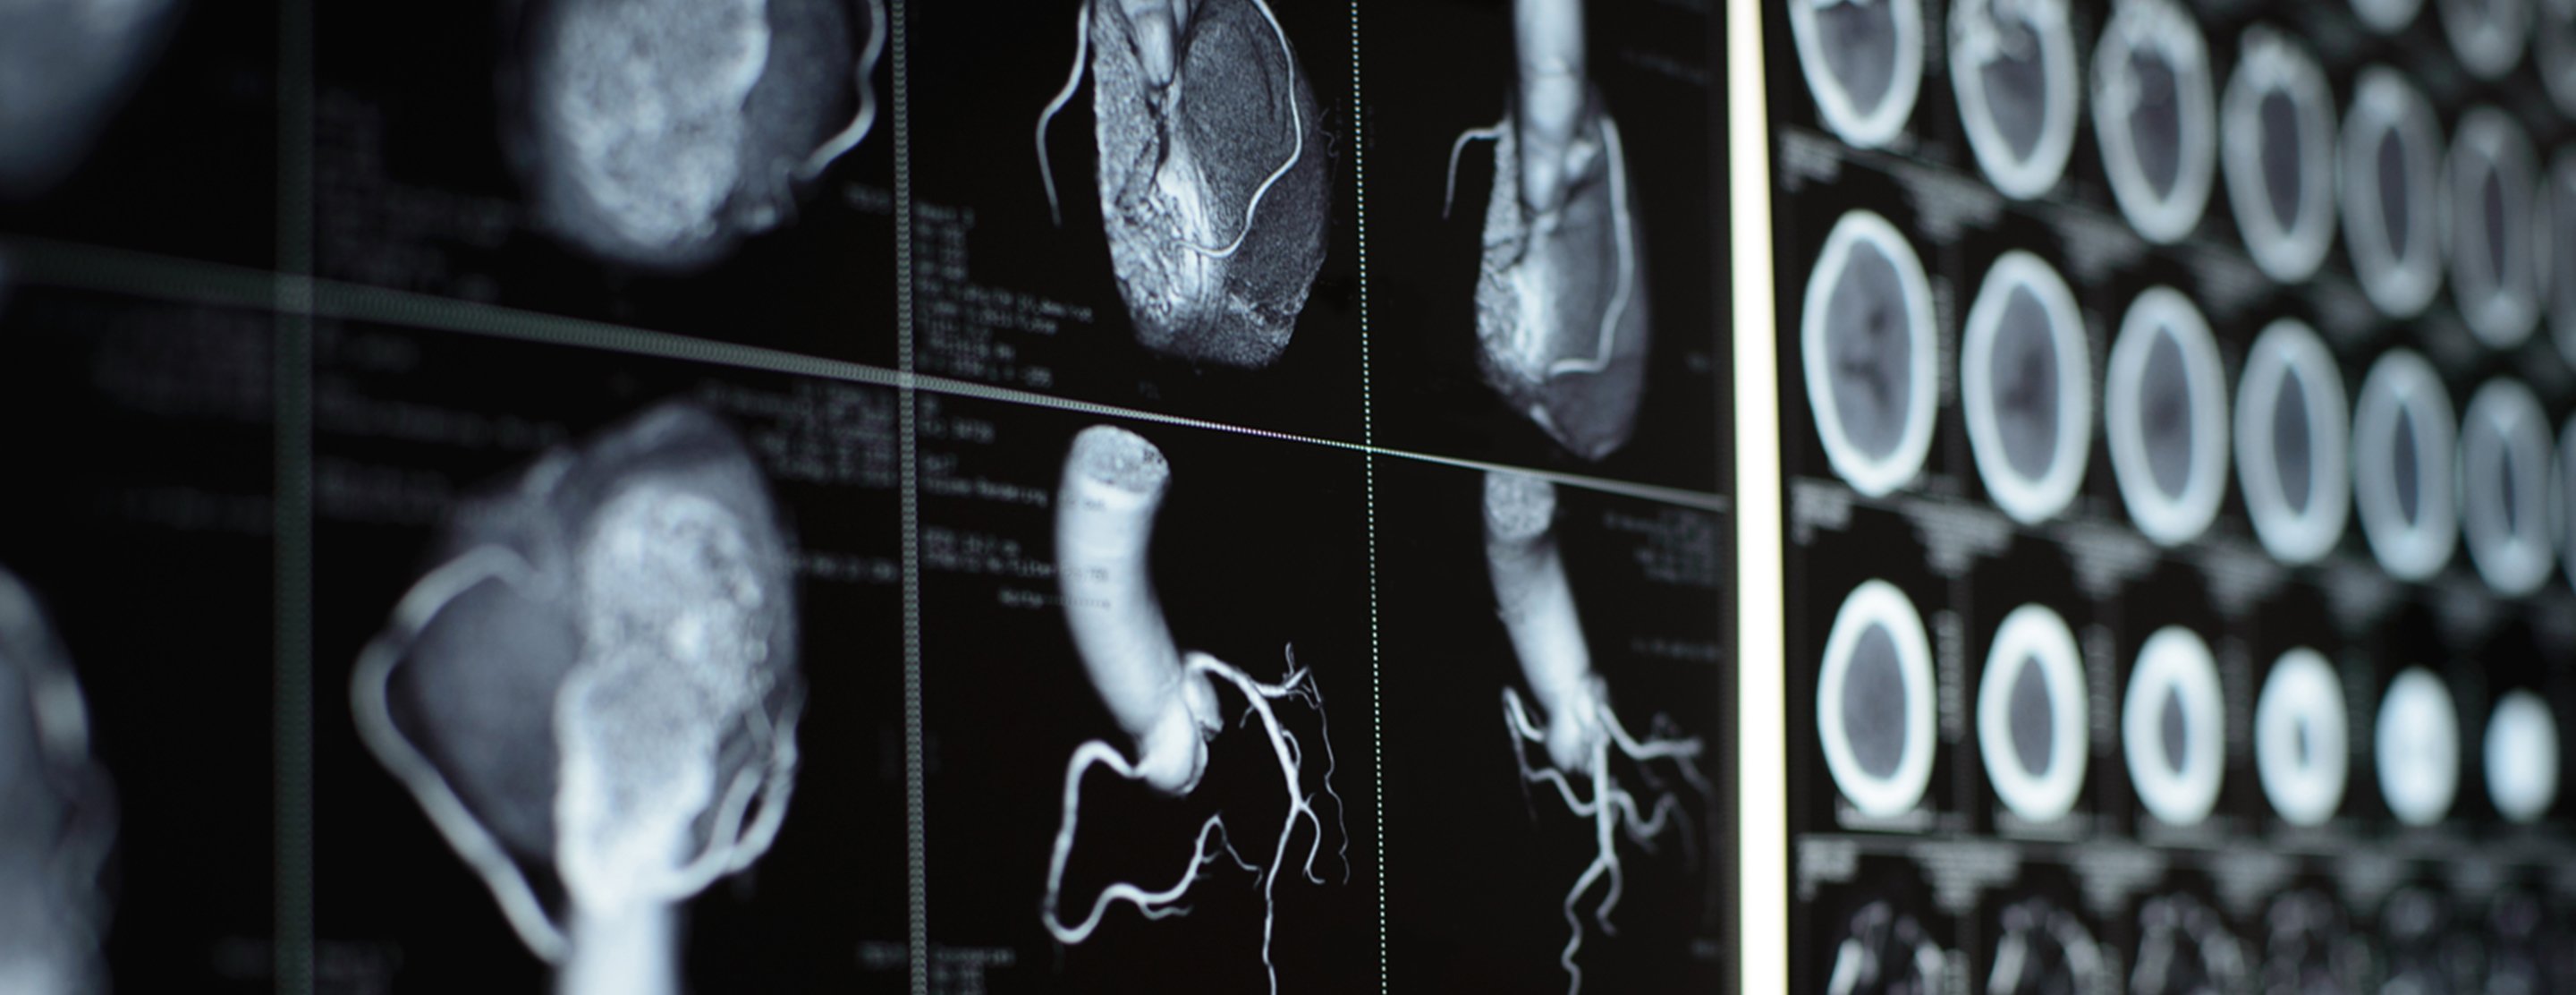

Heart CT scan

A computed tomography (CT) scan of the heart is an imaging method that uses x-rays to create detailed pictures of the heart and its blood vessels.

- It is called CT angiography if it is done to look at the arteries that bring blood to your heart. This test evaluates if there is narrowing or a blockage in those arteries.

- 3D (three-dimensional) models of the heart can be created.